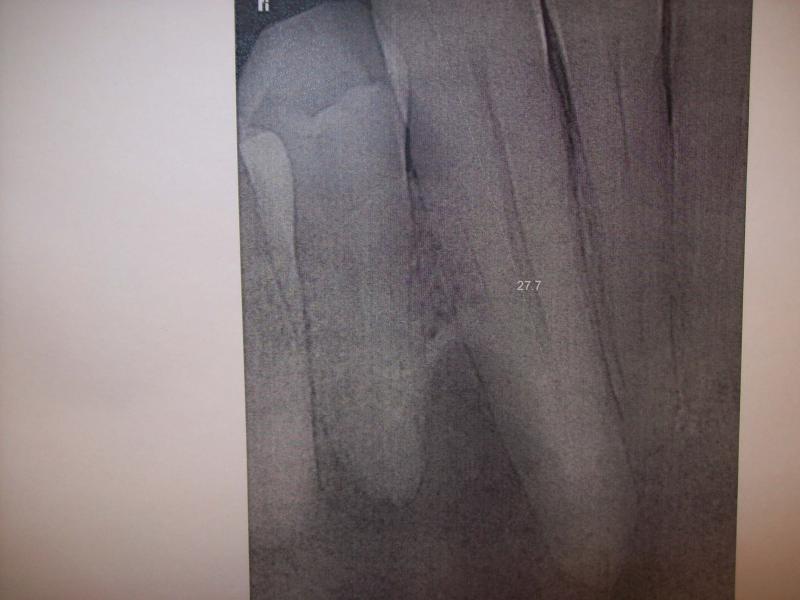

DR JET LOVES ROOT CANALS

General Dentist,  Performs Root Canals ONLY - Microscope Trained Dentist

"DR. JET'S MISSION IS TO PERFORM  ROOT CANALS FOR A REDUCED FEE USING THE LATEST TECHNOLOGY  AND TECHNIQUES TO SERVICE THE MANY PEOPLE WHO ARE UNINSURED OR UNDER-INSURED GIVING EVERYONE AN OPPORTUNITY TO SAVE THEIR TOOTH!"